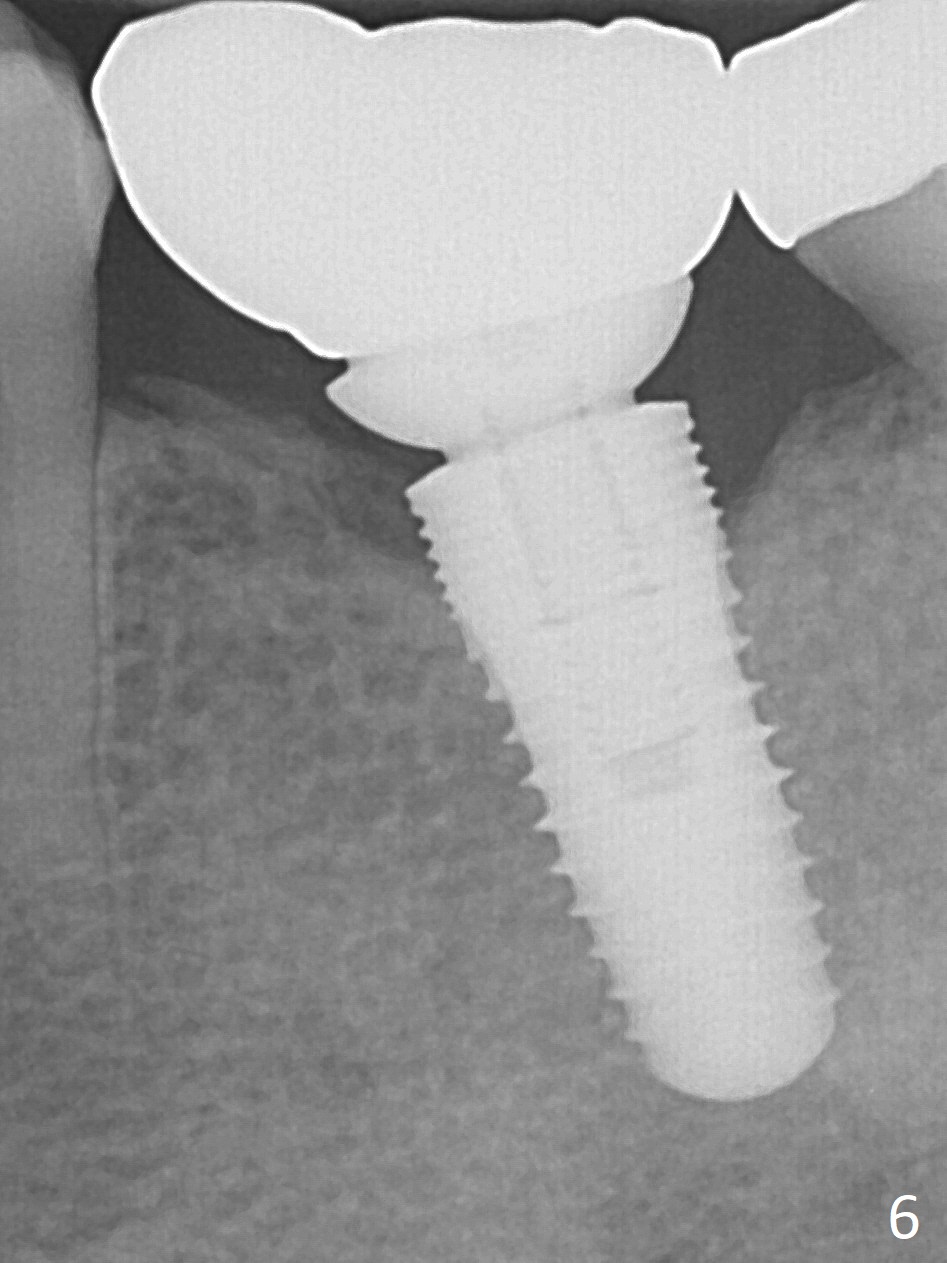

The edentulous ridge at #19 is moderately wide at the base, but pointed at the crest (Fig.1). After raising flaps, it appears that the ridge can hold a 5 mm implant using an implant positioner. The initial osteotomy is 12 mm deep and about 4 mm from the Inferior Alveolar Canal (Fig.2 yellow dashed line). Sequential osteotomy is carried out until 5x12 mm. Because of the pointed crest, 4.5 drill is used to extend the osteotomy at ~ 13 mm so that 12 mm implant can be placed a little deeper to reduce the amount of thread exposure. A 5.3x12 mm implant cannot be seated as deep as expected. A 5.3x10 mm drill with stopper is used before placing the same implant as mentioned above at the desirable depth (Fig.3). The insertion torque is > 60 Ncm. An abutment is placed immediately and an immediate provisional is fabricated and seated. Two to 3 microthreads buccally and lingually are covered by autogenous bone graft and collagen membrane. The patient returns for impression 4 months postop. There is bone loss distally (Fig.4 *). His oral hygiene is excellent. It is hoped that the bone loss will not get worse in the next visit.